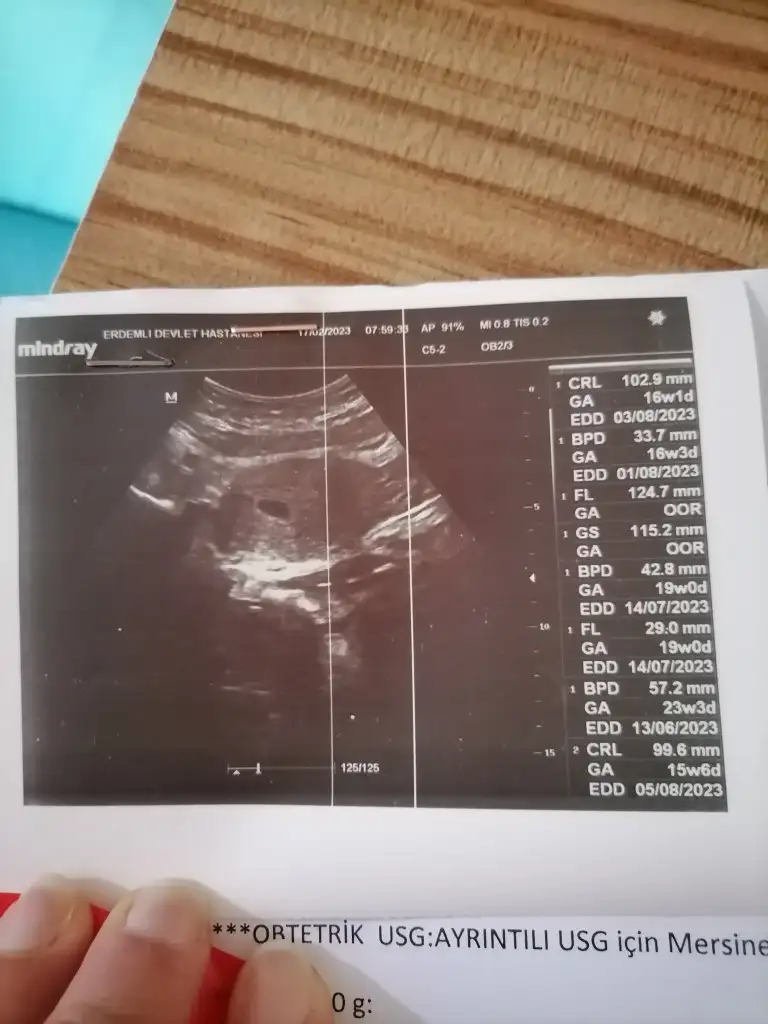

Yandaki bilgiler size ait değil maalesefEki Görüntüle 3210472

Sizin dediğim gibi ölçmemiş bebek boyunu sağdakiler nedir anlamadım genel bilgi falan olabilir. Bir dahaki sefere kalmış, olsun sağlıkla büyüsün de. Benim dediğim bu şekildeydi.Eki Görüntüle 3210472

Korkulacak birşey değil korkma bağışıklık bunlarArkadaşlar bu değerler ne anlama geliyor bilen var mı ? Çok korkuyorum